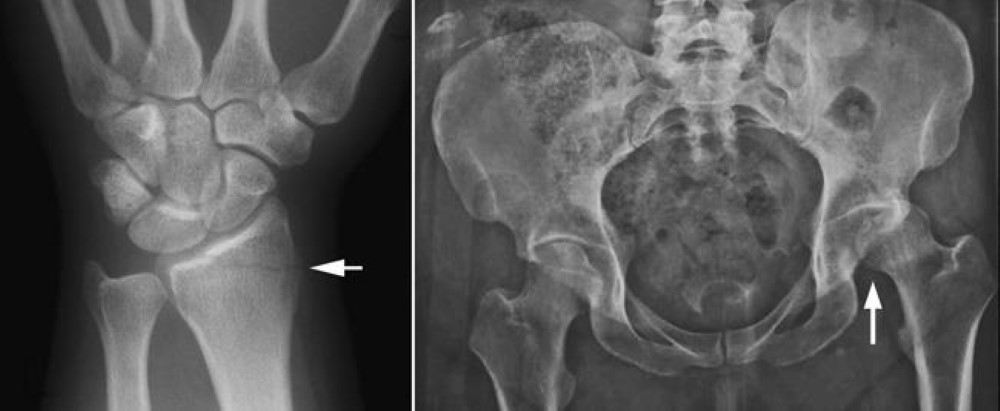

More concerning are X-rays of your lower torso like the abdomen pelvis or.

Bone Metastasis Of The Pelvis X Ray Stock Photo Alamy

Ankylosing Spondylitis X Ray Purpose Procedure And Management